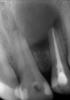

natikkk Опубликовано 7 декабря, 2010 Поделиться Опубликовано 7 декабря, 2010 Ситуация следующая: пациент обратился с жалобами на сильные ноющие боли и боли при накусывании в области передних зубов в/ч, данные жалобы появились примерно 3 дня назад, 2 дня назад обратился в другую клинику, где ему вскрыли 2.1 зуб, закрыли временной пломбой, которую было наказано снять при усилении болей, что пациент и сделал, т.к. боли после лечения ничуть не уменьшились, 2 ночи не спал и вот дошел до меняОбъективно: 2.1 - пломба медио-дистально, небно полость, канал открыт, незначительная подвижность в вестибуло-небном направлении, перкуссия слабо положительна; 2.2- небно-медиально состоятельная пломба, перкуссия положительна, незначительная подвижность в вест.-небном направлении; пальпация десны в области 2.1 и 2.2 безболезнена 2.1- канал обработан (коффердам, гипохлорит, ЭДТА, Соник), Каласепт, Клип; 2.2- распломбирован, обработан (то же самое), Каласепт, Клип. После обработки 2.2 высушился, а из 2.1 еще немного гноило, хотя мыла и обрабатывала оч. долгоКакая бы тактика лечения была у вас в таком случае? как думаете прогноз благоприятный? У нас главный врач сказала, что все бесполезно- надо удалять 2.2 Ссылка на комментарий

Большой Зеленый Опубликовано 12 декабря, 2010 Поделиться Опубликовано 12 декабря, 2010 ну если не резекцию то цистэктомию однозначно, все будет видно интрооперационно+1 сильно большая дырка. Ссылка на комментарий

Мартовский Опубликовано 12 декабря, 2010 Поделиться Опубликовано 12 декабря, 2010 Я даже где то здесь вывешивал, причём обтурация была с охрененным овером. Всё заросло.Ещё раз выкладываюhttp://s39.radikal.ru/i084/1005/4e/cc0c25ced000.jpghttp://s55.radikal.ru/i147/1005/4b/5f07a406217e.jpghttp://s003.radikal.ru/i204/1005/13/89f2b4fe63a4.jpg Это то что под рукой было. И гораздо бОльшие дырки зарастали, размер не имеет значения. Ссылка на комментарий